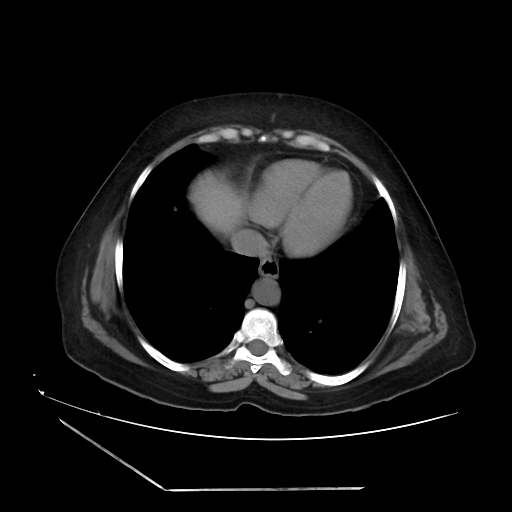

A 70 years old woman with Obstractive jaundice & palpable GB